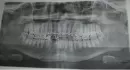

Прошло 30 дней с операции шинирования. Обратился к частному врачу стоматологу, так как лечащий врач в отпуске. Врач, посмотрев ортопанорамный снимок, сказал мне, что шинирование установлено правильно, но идет неправильное срастание. Нужно пере шинировать челюсть, но пока рано снимать шины.

Правильный ли вердикт частного врача?

Вопрос в том, почему шины не установлены во фронтальном отделе нижнего зубного ряда. Рекомендуем обратиться к квалифицированному челюстно-лицевому хирургу.